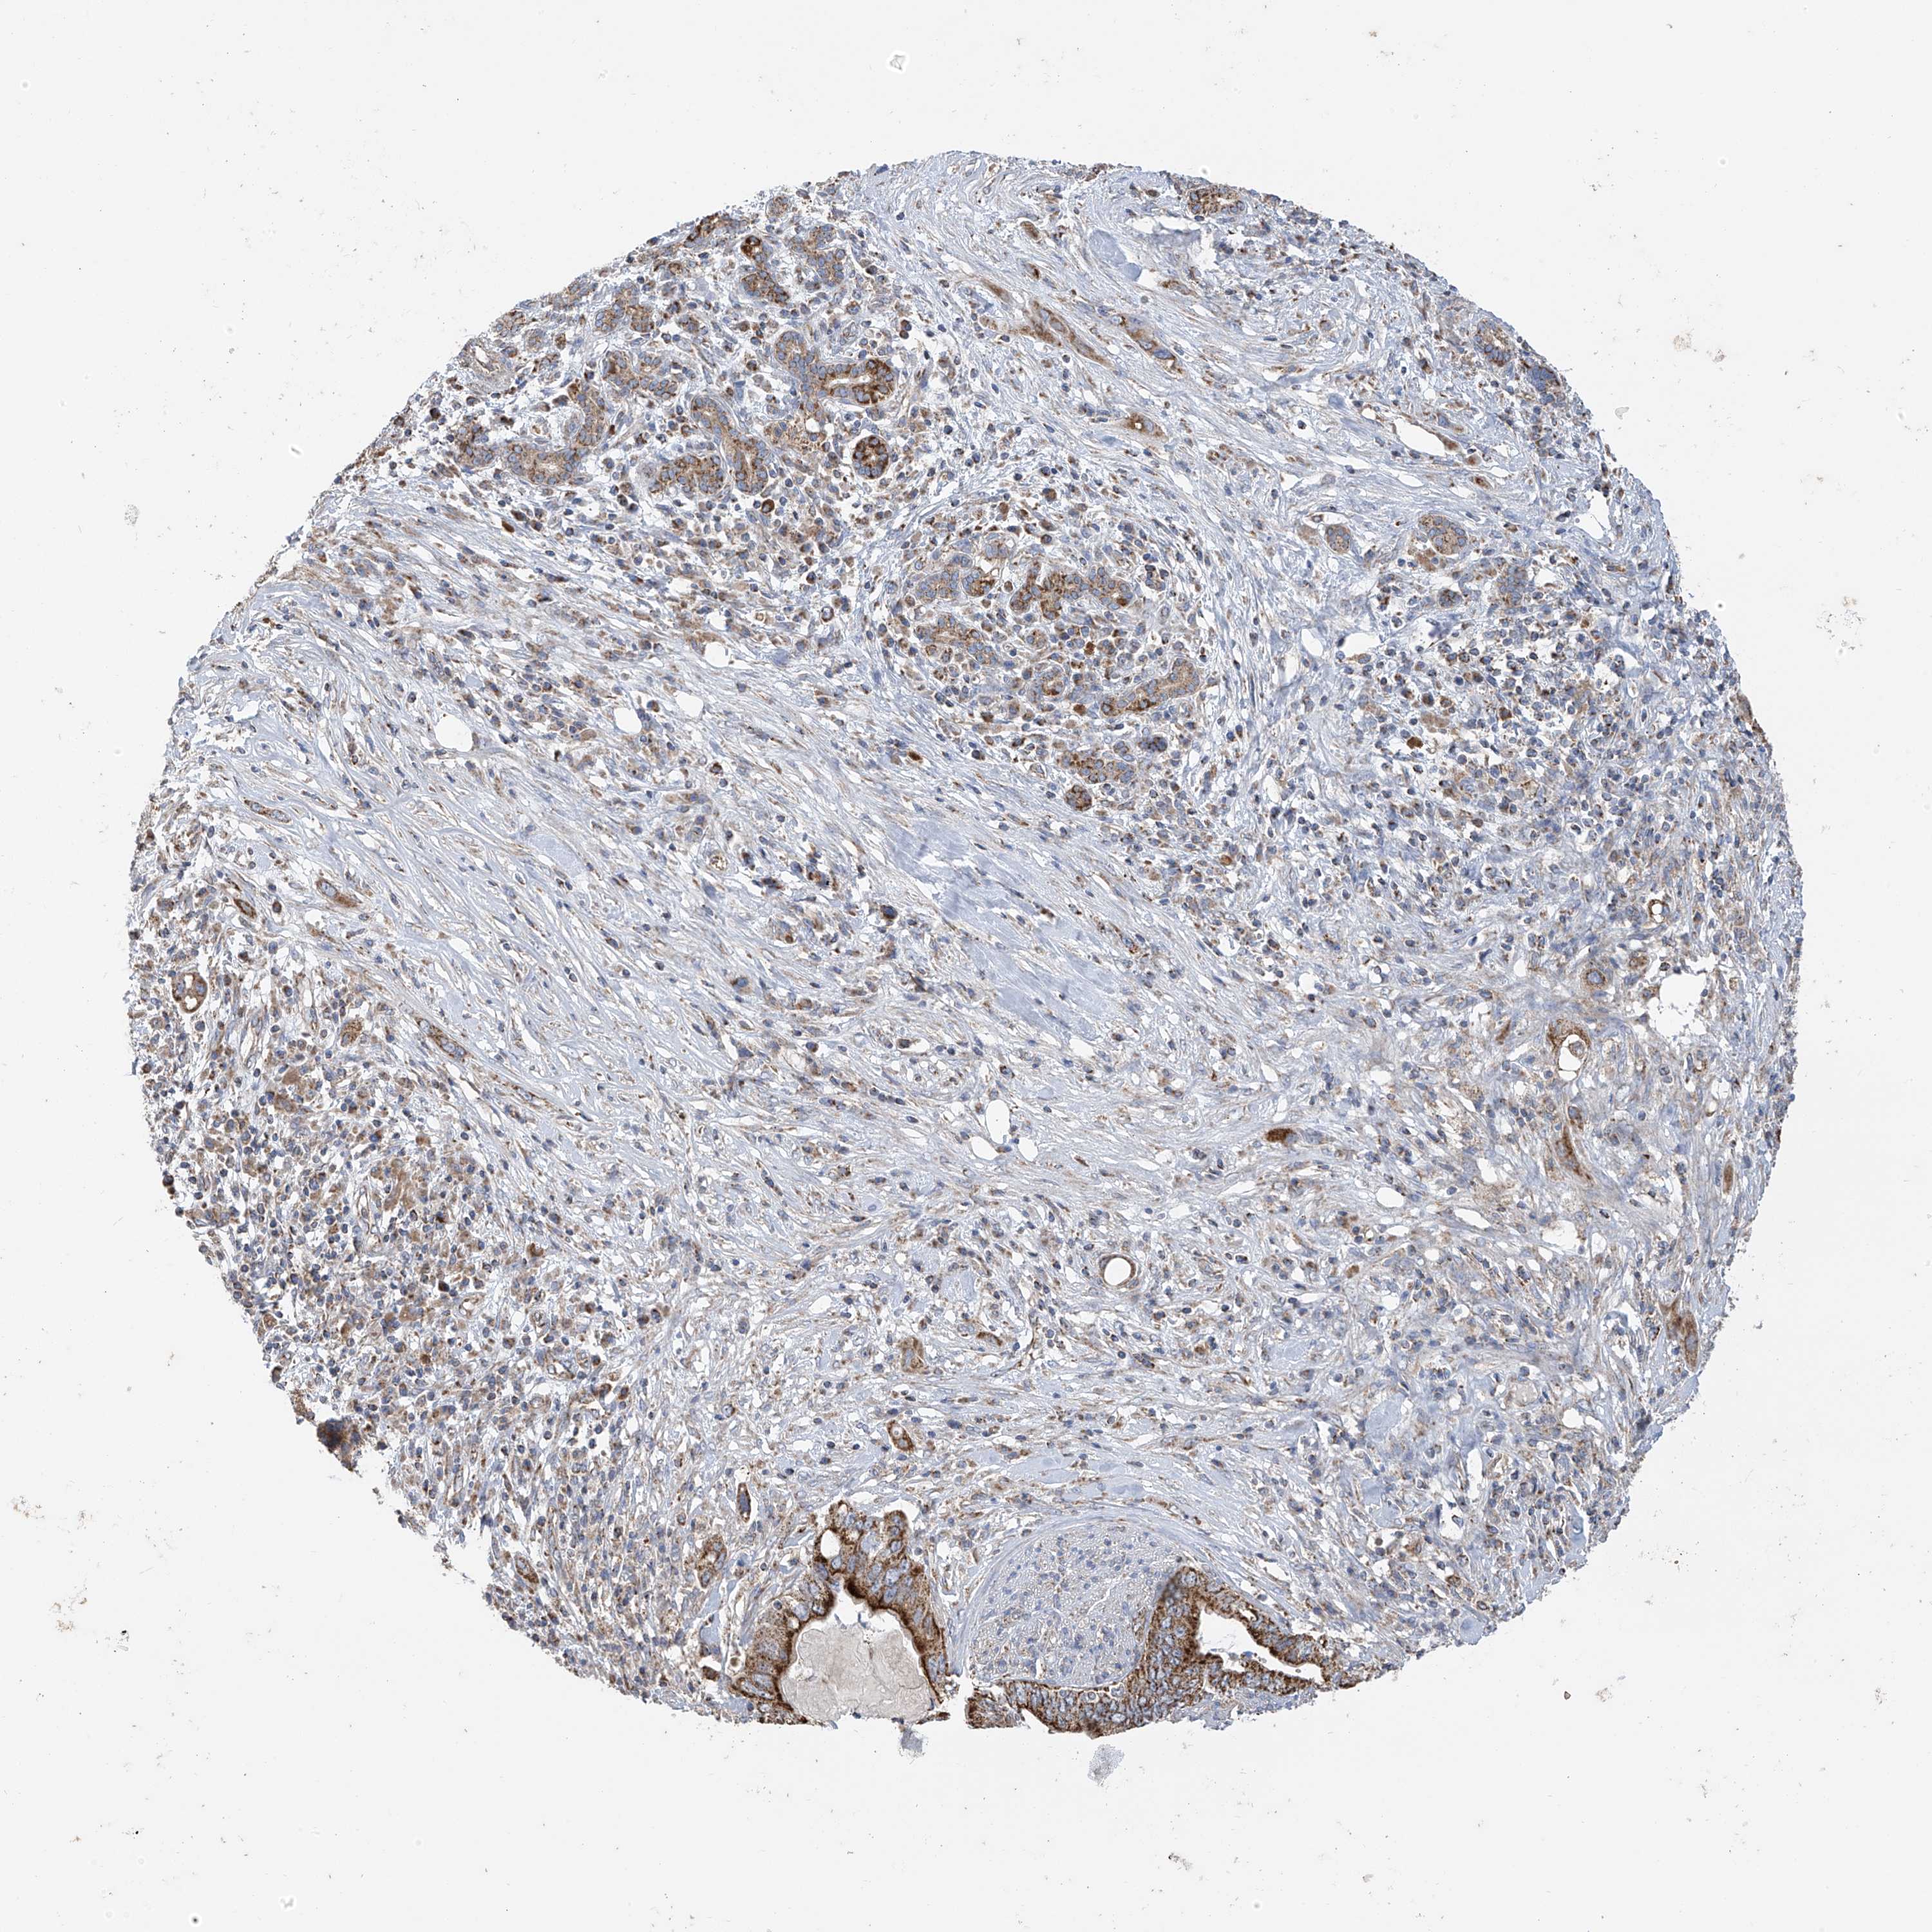

PANCREATIC CANCER - Protein expressioni

A mouse-over function shows sample information and annotation data. Click on an image to view it in a full screen mode. Samples can be filtered based on level of antibody staining by selecting one or several of the following categories: high, medium, low and not detected. The assay and annotation is described here.

Note that samples used for immunohistochemistry by the Human Protein Atlas do not correspond to samples in the TCGA dataset.

Antibody stainingi

Antibody staining in the annotated cell types in the current human tissue is reported as not detected, low, medium, or high, based on conventional immunohistochemistry profiling in selected tissues. This score is based on the combination of the staining intensity and fraction of stained cells.

Each image is clickable and will lead to virtual microscopy that enables deeper exploration of all samples and also displays staining intensity scores, fraction scores and subcellular localization as well as patient and tissue information for each sample.

Antibody HPA034602

Antibody HPA034603

Antibody CAB033424

Staining

High

Medium

Low

Not detected

Intensity

Strong

Moderate

Weak

Negative

Quantity

>75%

75%-25%

<25%

None

Location

Nuclear

Cytoplasmic/membranous

Cytoplasmic/membranous,nuclear

Adenocarcinoma, NOS